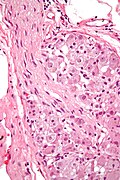

Ganglion cell

- Nerve cell body.

- Found in ganglions - encapsulated body ~ 100-300 μm.

- Large round nucleus with prominent nucleolus - key feature.

- Abundant eosinophilic granular cytoplasm.

Schwann cell

- Principal glia of the PNS.

- Myelinated or unmyelinated.

- Ovoid, wavy nuclei.

- Cells have a basal membrane.

- Found in peripheral nerves.

- Aka neurolemmocytes.

- Ganglion very high mag.jpg

Ganglion - very high mag. (WC/Nephron)